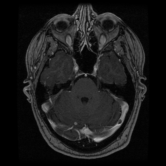

The category discovery clusters employing our LDPO method are found to be more visually coherent and cluster-wise balanced in comparison to the results in [44] where clusters are formed only from text information ( radiology reports). Fig. 4 Left shows the image numbers for each cluster from the AlexNet-FC7-Topic setting. The numbers are uniformly distributed with a mean of 778 and standard deviation of 52. Fig. 4 Right illustrates the relation of clustering results derived from image cues or text reports [44]. Note that there is no instance-balance-per-cluster constraints in the LDPO clustering. The clusters in [44] are highly uneven: 3 clusters inhabit the majority of images. Fig. 5 shows sample images and top-10 associated key words from 4 randomly selected clusters (more results in the supplementary material). The LDPO clusters are found to be semantically or clinically related to the corresponding key words, containing the information of (likely appeared) anatomies, pathologies (e.g., adenopathy, mass), their attributes (e.g., bulky, frontal) and imaging protocols or properties.

Next, from the best performed LDPO models in Table 2, AlexNet-FC7-Topic has Top-1 classification accuracy of 0.8109 and Top-5 accuracy 0.9412 with 270 formed image categories; AlexNet-FC7-ImageNet achieves accuracies of 0.8099 and 0.9547, respectively, from 275 discovered classes. In contrast, [44] reports Top-1 accuracies of 0.6072, 0.6582 and Top-5 as 0.9294, 0.9460 on 80 text only computed classes using AlexNet [27] or VGGNet-19 [47], respectively. Markedly better accuracies (especially on Top-1) on classifying higher numbers of classes (being generally more difficult) highlight advantageous quality of the LDPO discovered image clusters or labels. This means that the LDPO results have rendered significantly better performance on automatic image labeling than the most related previous work [44], under the same radiology database. After the subjective evaluation by two board-certified radiologists, AlexNet-FC7-Topic of 270 categories and AlexNet-FC7-ImageNet of 275 classes are preferred, out of total six model-encoding setups. Interestingly, both CNN models have no deep feature encoding built-in and preserve the gloss image layouts (capturing somewhat global visual scenes without unordered FV or VLAD encoding schemes [9, 8, 21].).